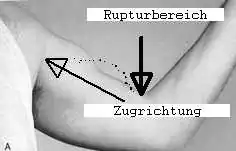

Distale Bizepssehnenruptur

- Akuter starker Schmerz

- Peitschenknallartiges Geräusch

- Functio laesa (Funktionsverlust), Flexion und Supination im Ellbogengelenk nicht mehr durchführbar (insgesamt deutlicher Kraftverlust)

- Tastbare Delle im Rupturbereich des Sehnenverlaufs, in die sich Blut ergießt und somit ein Hämatom[7] bildet

- Entstehung einer proximalen Schwellung bzw. Verlagerung des Muskelbauches in Richtung Schulter bei Muskelkontraktion[7]